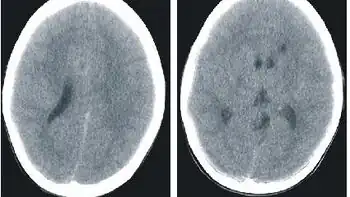

.jpg.webp)

Histidenemia is characterized by increased levels of histidine, histamine and imidazole in blood, urine and cerebrospinal fluid. This also results in decreased levels of the metabolite urocanic acid in blood, urine, and skin cells.[1]

In Japan, neonatal screening was previously performed on infants within one month of birth; infants demonstrating a blood histidine level of 6 mg/dl or more underwent careful testing as suspected histidinemia cases.[6]

A typical characteristic of histidinemia is an increase in the blood histidine levels from normal levels (70–120 μM) to an elevated level (290–1420 μM).[3] Further testing includes: observing histidine as well as imidazolepyruvic acid metabolites in the urine. However, neonatal urine testing has been discontinued in most places, with the exception of Quebec.[3]